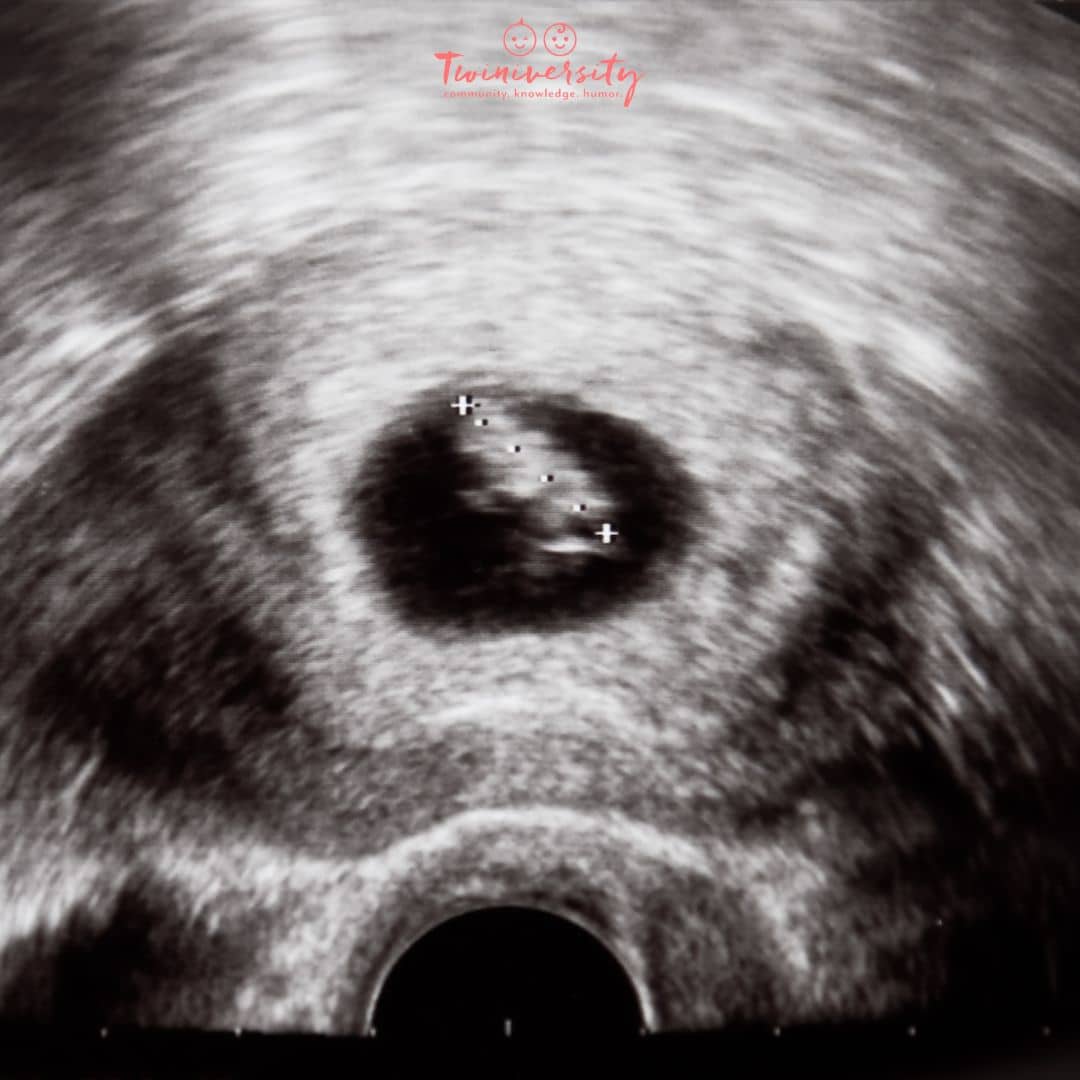

The HCG Levels That Could Mean You're Having Twins | Twiniversity #1

The hCG Levels That Could Mean You're Having Twins | Twiniversity #1 www.twiniversity.com

The HCG Levels That Could Mean You're Having Twins - Twiniversity

The hCG Levels That Could Mean You're Having Twins - Twiniversity www.twiniversity.com